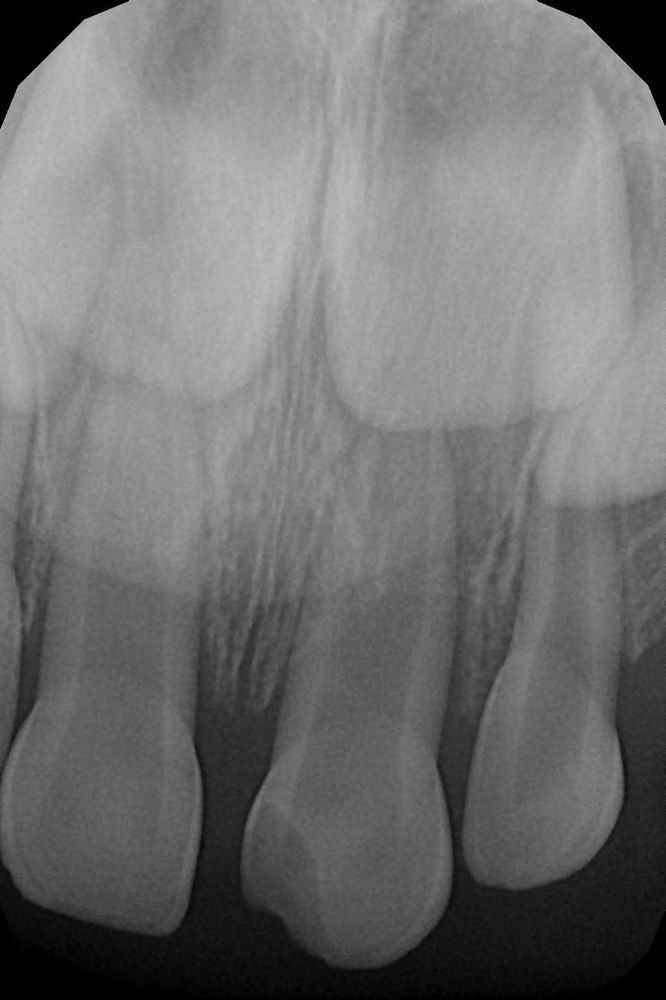

месяц назад дочь(2,4) упала со спинки дивана, и приземлилась зубами о плитку. Была кровь, шла носом, и скололся передний зуб🙁. долго плакала, страх короче. Поехали мы в докдети , сделали снимок, сказали наблюдать, корень цел , и трещин на зубе нет. Через дней 5 мы еще поехали в морозовскую, проверить нос, дочь жаловалась, решили показать, сказали все хорошо.

и вот прошло три недели, мы поехали к дедушке в гости, вечером ор, истерика, я даже и не сразу поняла что болит зуб, кое как уложила, но дочь просыпалась и дико орала каждые два часа, даже не удавалось дать нурофен. Утром проснулась с отеком верхней губы, там где сколот зуб, и щека немного припухла, десна красная, тоже припухла. мы поехали домой, в Москву. Вот сегодня посетили стоматолога, долго она крутила снимок, и вердикт вынесла-ПОД УДАЛЕНИЕ!! Были мы снова в докдети, начался воспалительный процес в ткани, может повредить зачатки постоянного зуба, это очаг инфекции и может выстрелить в любой момент. Предложили удаление под наркозом. Остальные зубы у нас хорошие, лечения не требуют!!! Вот такой вопрос !!!